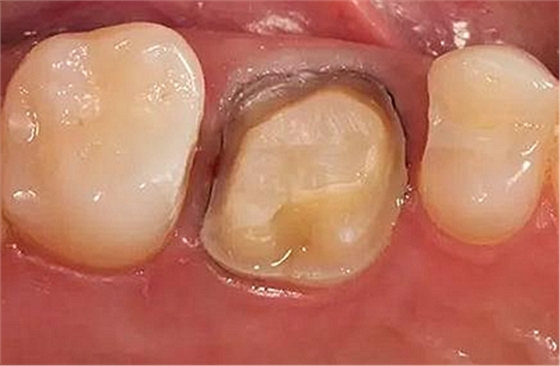

步驟3

牙體制備完成后的牙合面觀

牙合面觀察牙體預(yù)備之后的情況。

軸壁按要求預(yù)留0.8 mm 寬度。